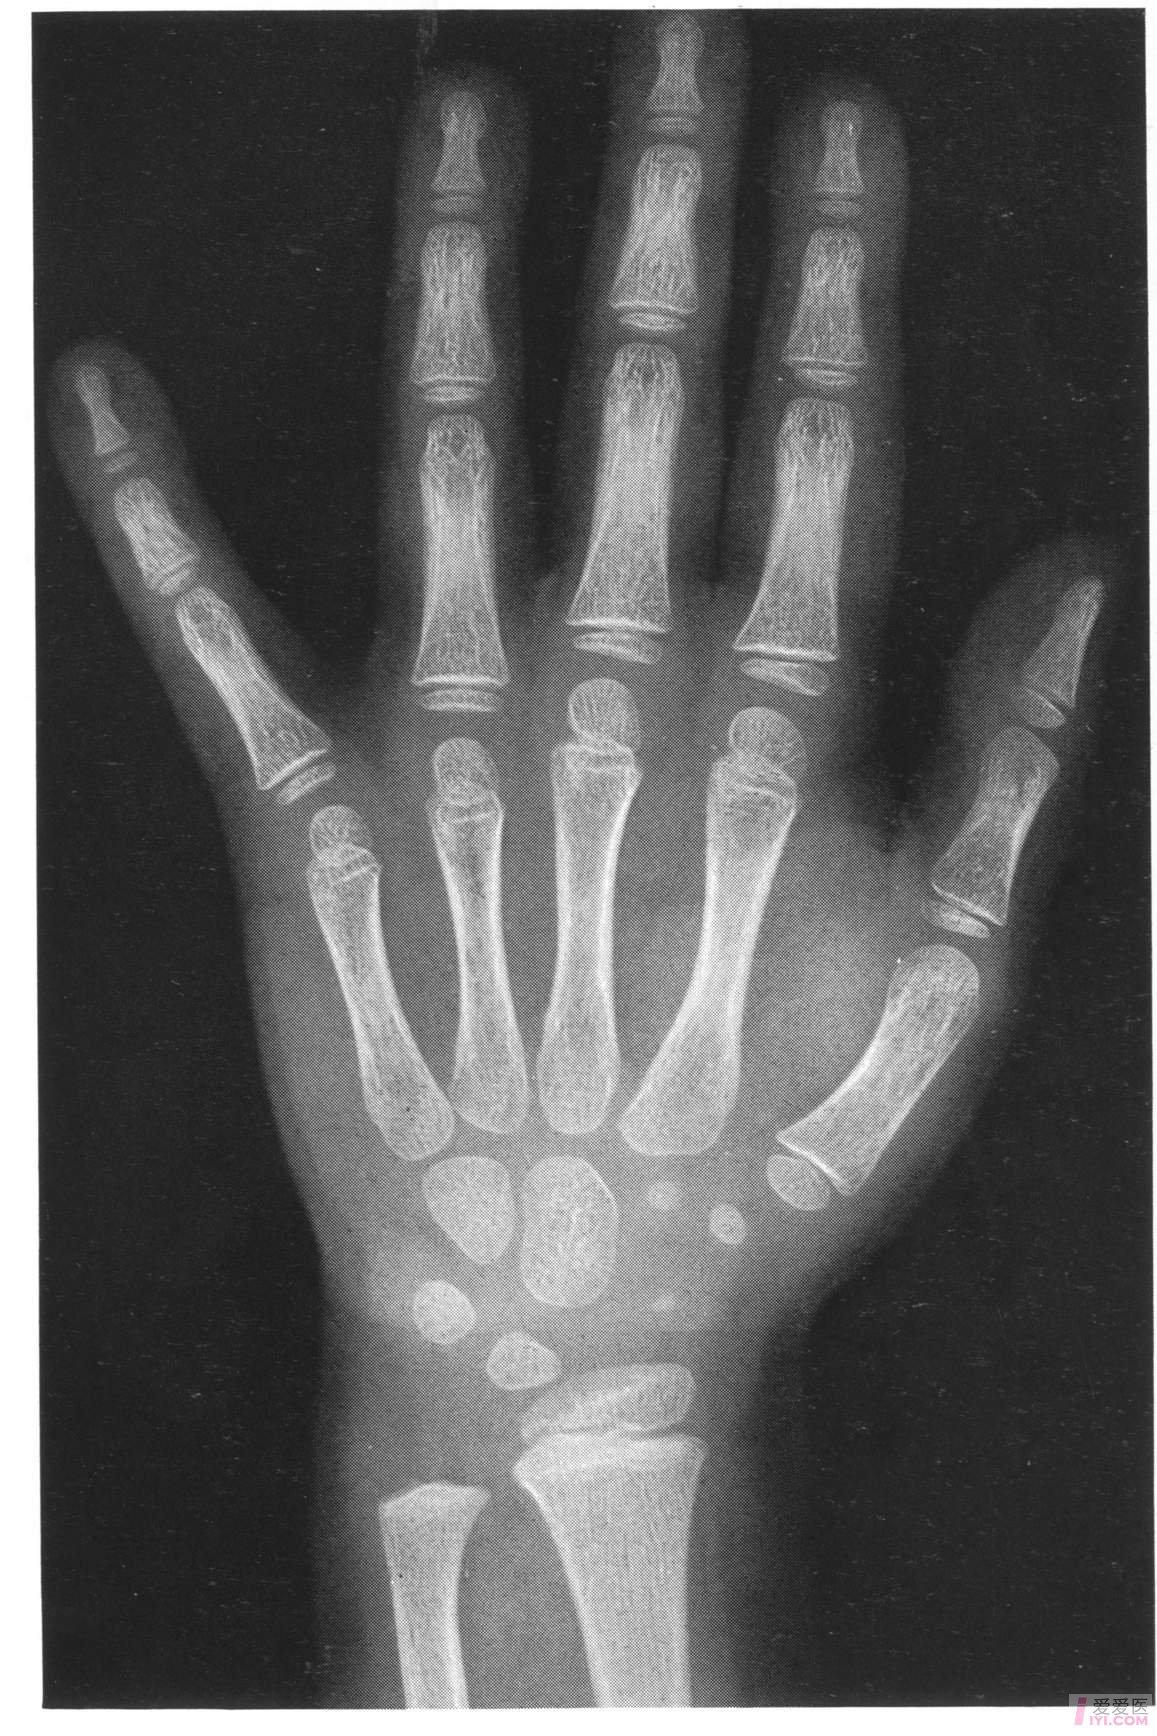

帮忙看看这个骨龄片,12周岁六个月的男孩子,骨龄片上显示骨龄多少岁?

简单说,骨龄就是骨骼年龄,通常是拍摄左手手腕的x光片,医生会通过x光

手,腕部骨成熟度,2.骨龄≠实际年龄,3.骨骼身高≠实际年龄.

骨骼的形态,大小都会有所变化,而 这种变化可以通过x光检查来观察

中国儿童标准骨龄片